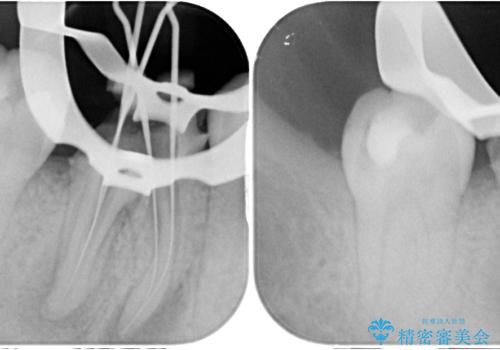

レントゲン写真などの診察を行った結果、根管治療が必要であったため、現在のクラウンを除去し、根管治療を行うこととしました。

根管治療後は症状を確認し、速やかにオールセラミッククラウンにて補綴治療を行うこととしました。

病変が消退しているかどうか、半年、1年とレントゲン写真で経過観察を行う必要があります。

海外に行かれていた都合で、術後2年での経過観察となりましたが、無事に病変の消失が認められました。